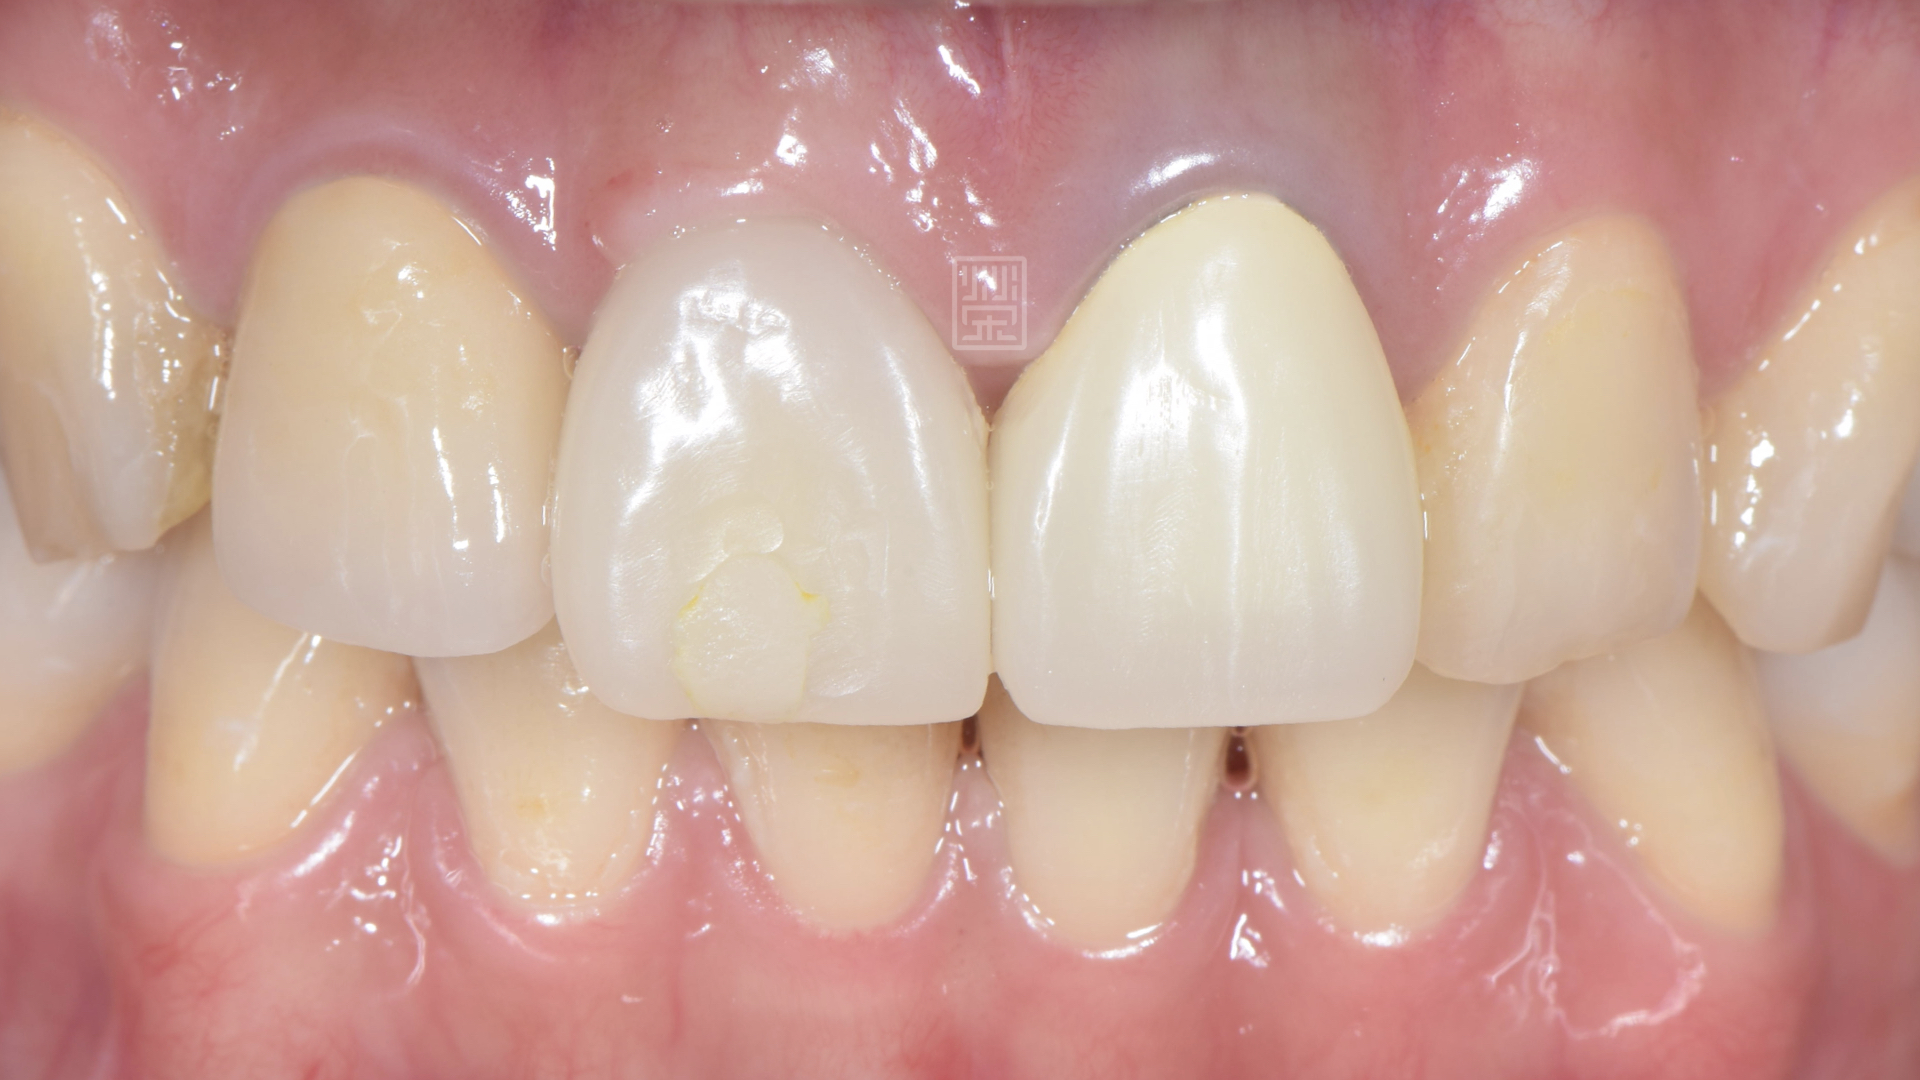

全瓷冠完成